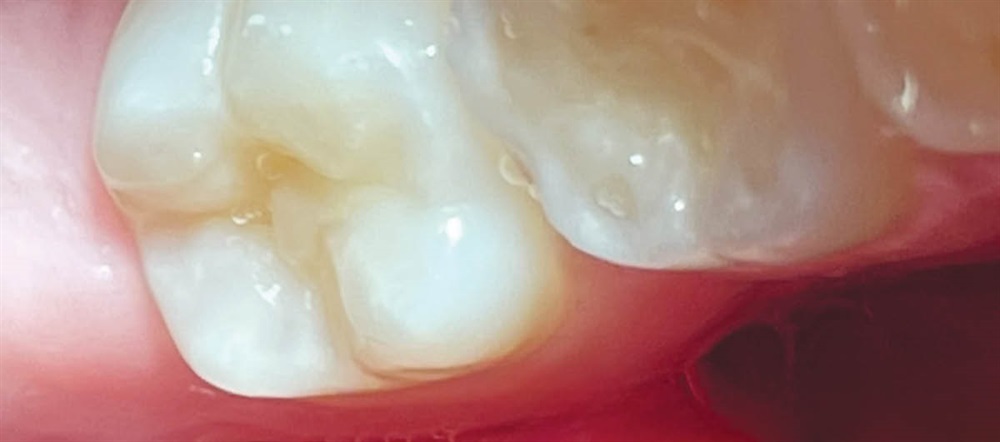

Patient 1: Buccal use

Curadont Cases

Fig. 1: A 9-year-old boy with buccal gumline decalcification on his first permanent molar.

Fig. 2: After cleaning the tooth, 37% phosphoric etch was applied for 20 seconds, then rinsed with water and dried.

Fig. 3: Curodont was applied and allowed to absorb for five minutes.

Fig. 4: A 16-month follow-up photo shows the buccal aspect of the tooth has not cavitated and the enamel translucency has improved.